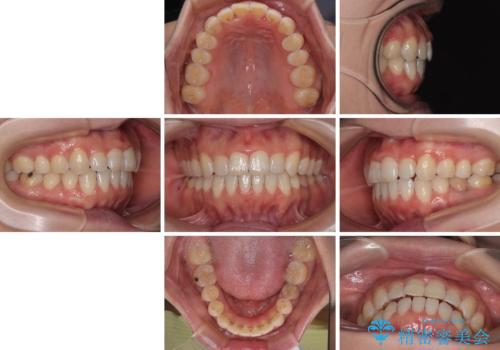

【モニター】飛び出した上顎前歯 補助装置を併用したインビザライン矯正治療

補助装置なしでも改善できる可能性はありましたが、補助装置で確実性を上げ、短期間できっちりと仕上げることができました。

- 上下前歯が非接触となり、前方に突出していることを気にして来院された患者様です。

上下の前後差が大きいため、インビザライン単独での上顎歯列移動は困難と判断し、補助装置により上顎歯列を後方移動させ、その後インビザラインにて仕上げていくこととしました。